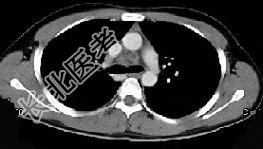

- 女,64岁, 胸背疼痛一周,CT检查如图